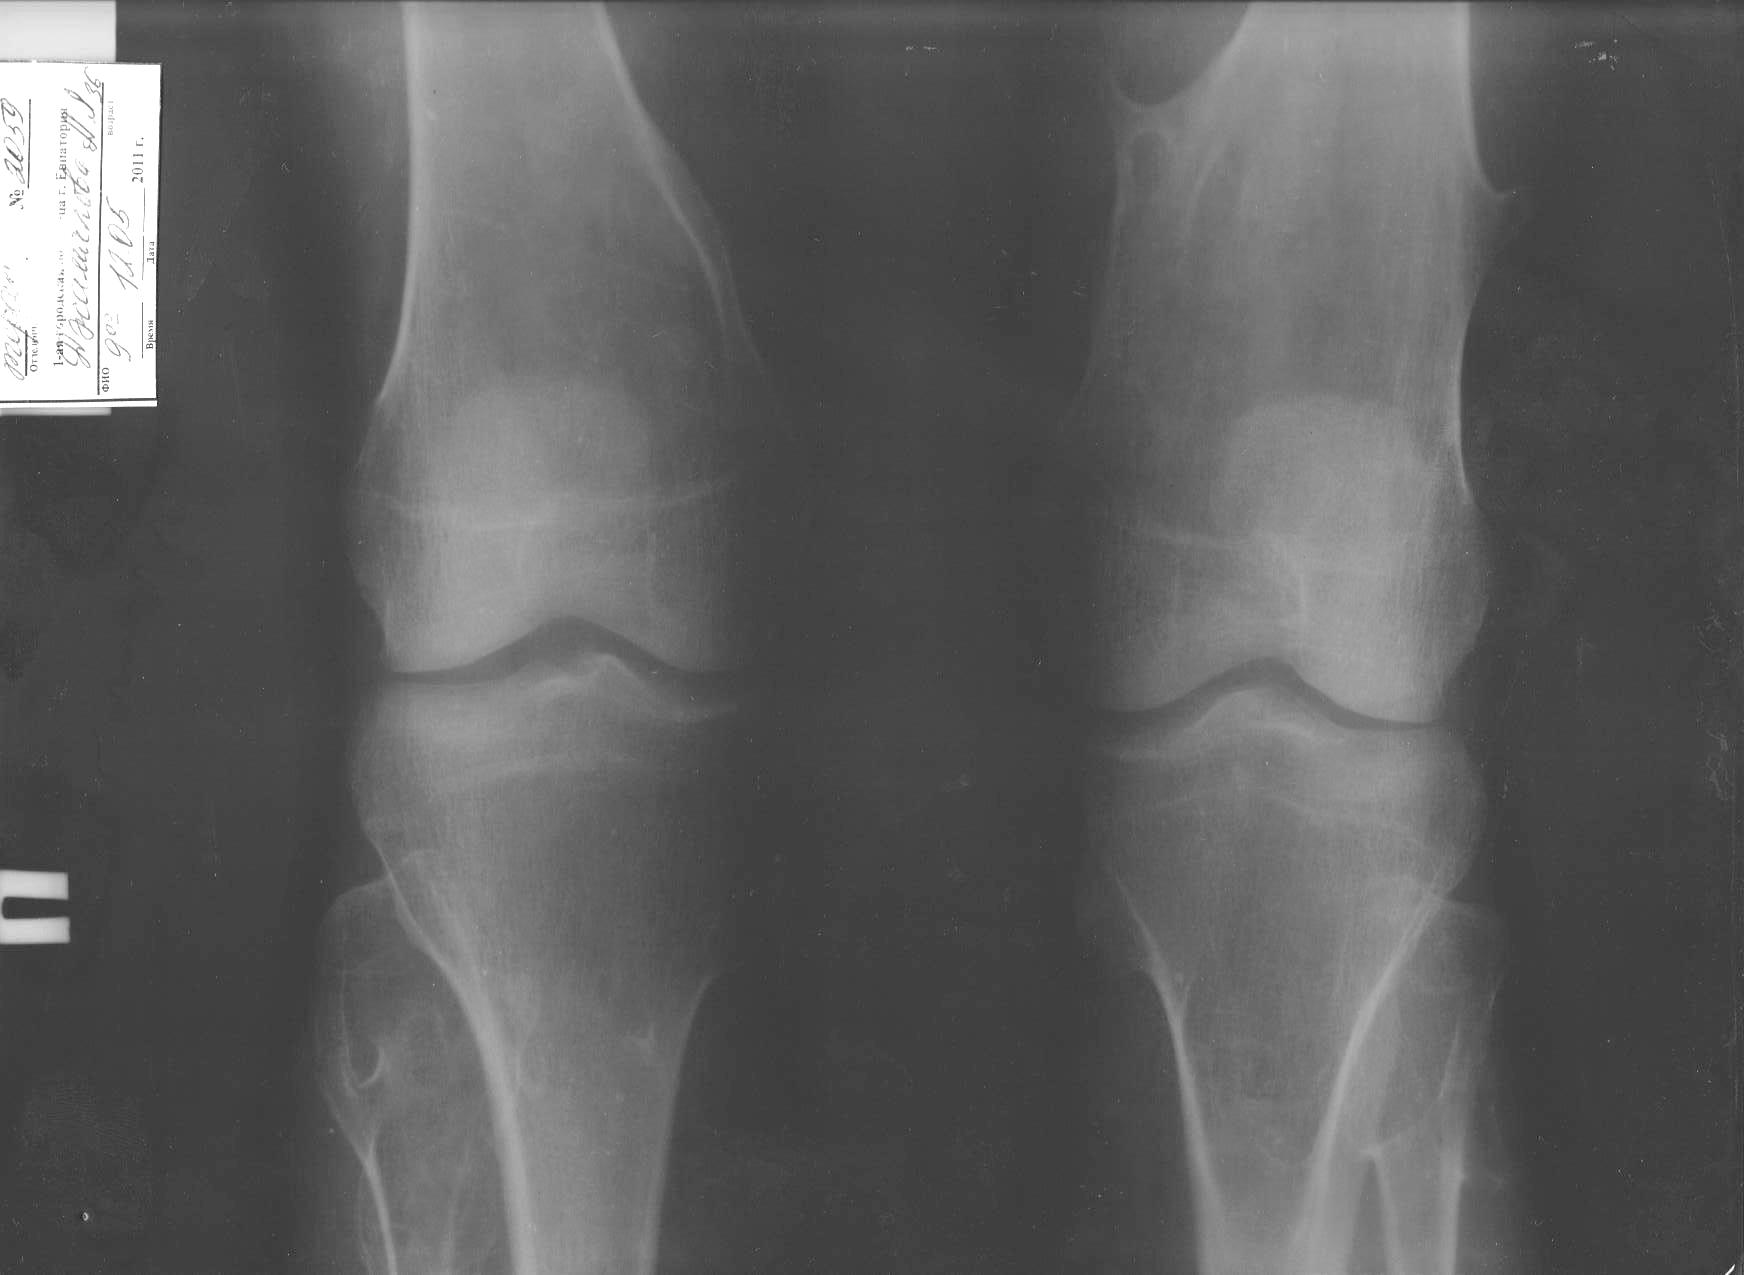

Уважаемые коллеги! Обратились за помощью ревматологи - больная 37 лет, низкого (меньше 150 см) роста, болеет несколько лет: преходящие боли в коленных суставах, суставах кистей. Ставился диагноз "ревматоидный артрит", но со слов ревматолога она не совсем на  него "клеится". На данный момент беспокоят боли в области коленных суставов, гиперестезия кожи по передне-наружной поверхности обоих бедер. Периартикулярный отек умеренный, жидкости в суставах не определяется, движения несколько ограничены. На гормонах боли уменьшаются. Сделали Р-графию - получили такую картину.

Может кто-нибудь встречал подобное? Мысли в плане дообследования?